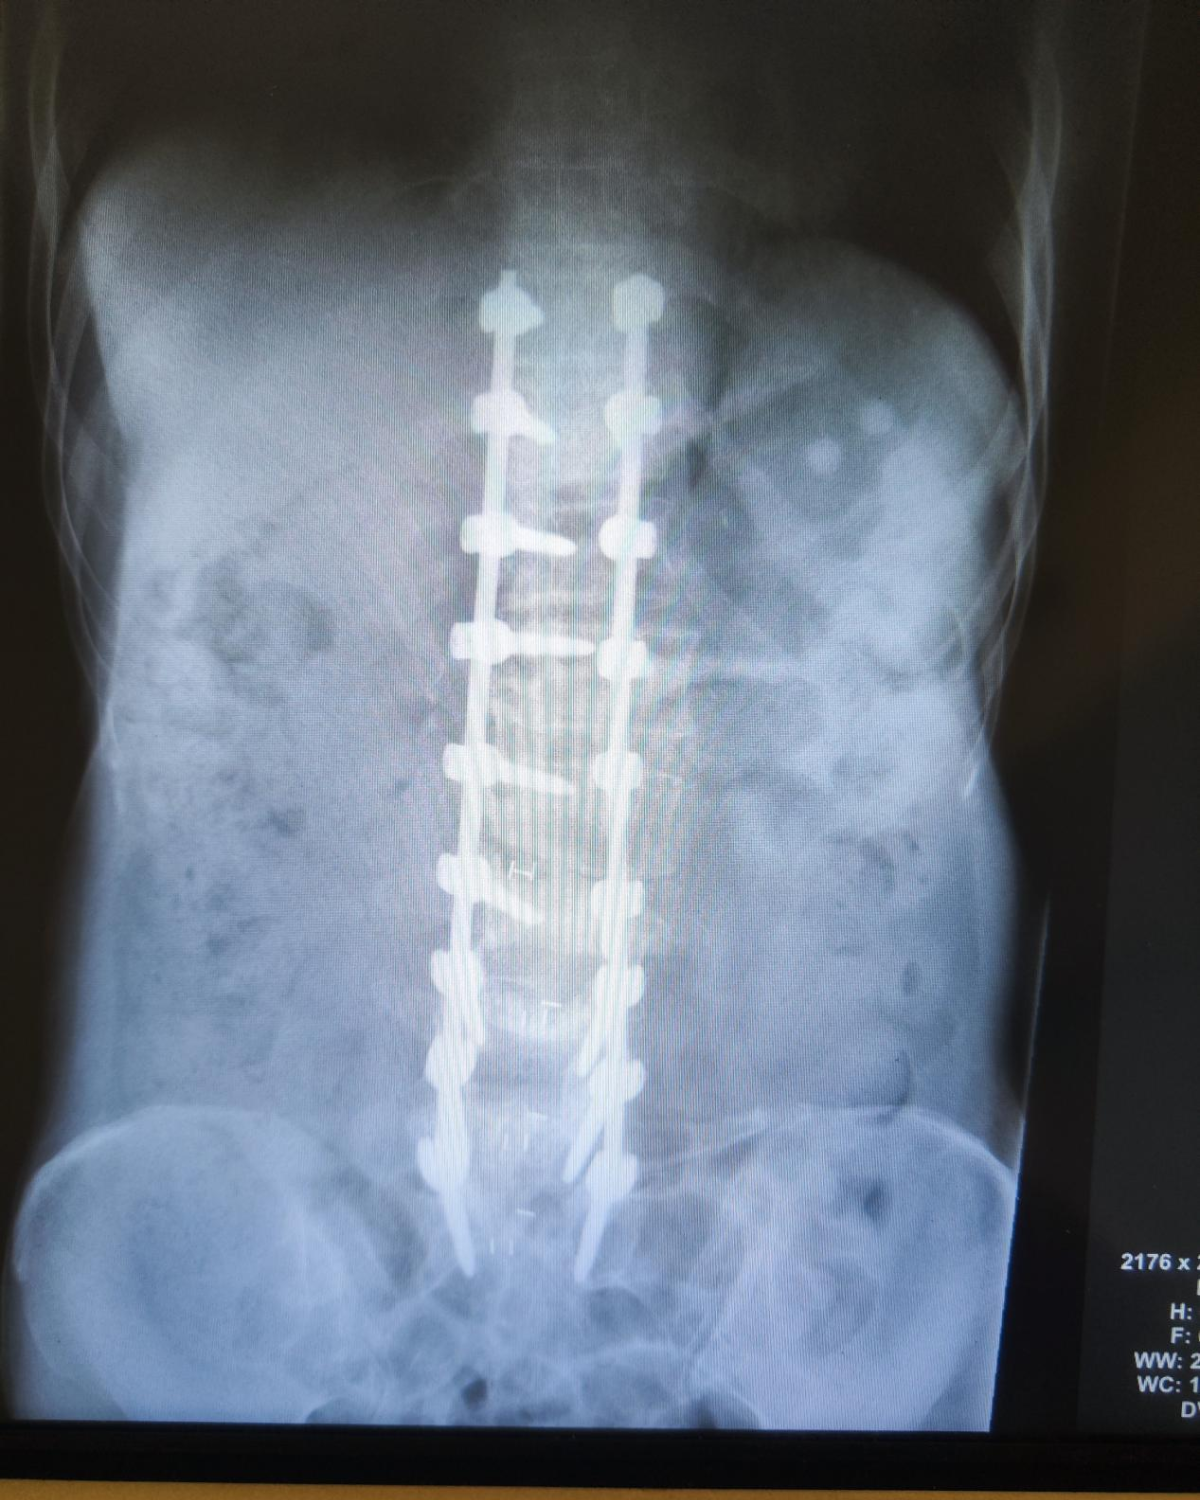

因为常年脊柱侧弯并旋转畸形,周围增生异常严重,正常的解剖结构无法辨别,完全靠经验来完成操作。手术过程异常艰难,但病人的信任是所有参与人员全力以赴的动力。历经7个多小时手术,弯曲的脊柱变直了,狭窄的腰椎椎管和受压的神经根得到了充分的减压。

术后患者肢体活动正常,没有神经受损的情况。经历了前几天的发热,血糖不稳定,低蛋白血症,离子紊乱等并发症,逐渐各项指标都调整正常了。术后第7天,引流管拔除后,桑大姐佩戴支具顺利地下床活动,原来剧烈的腰腿疼症状消失了,她非常高兴,并且打趣说,不但腰杆直了,还比原来高了4、5公分。她爽朗的笑声是对治疗效果最好的回答。